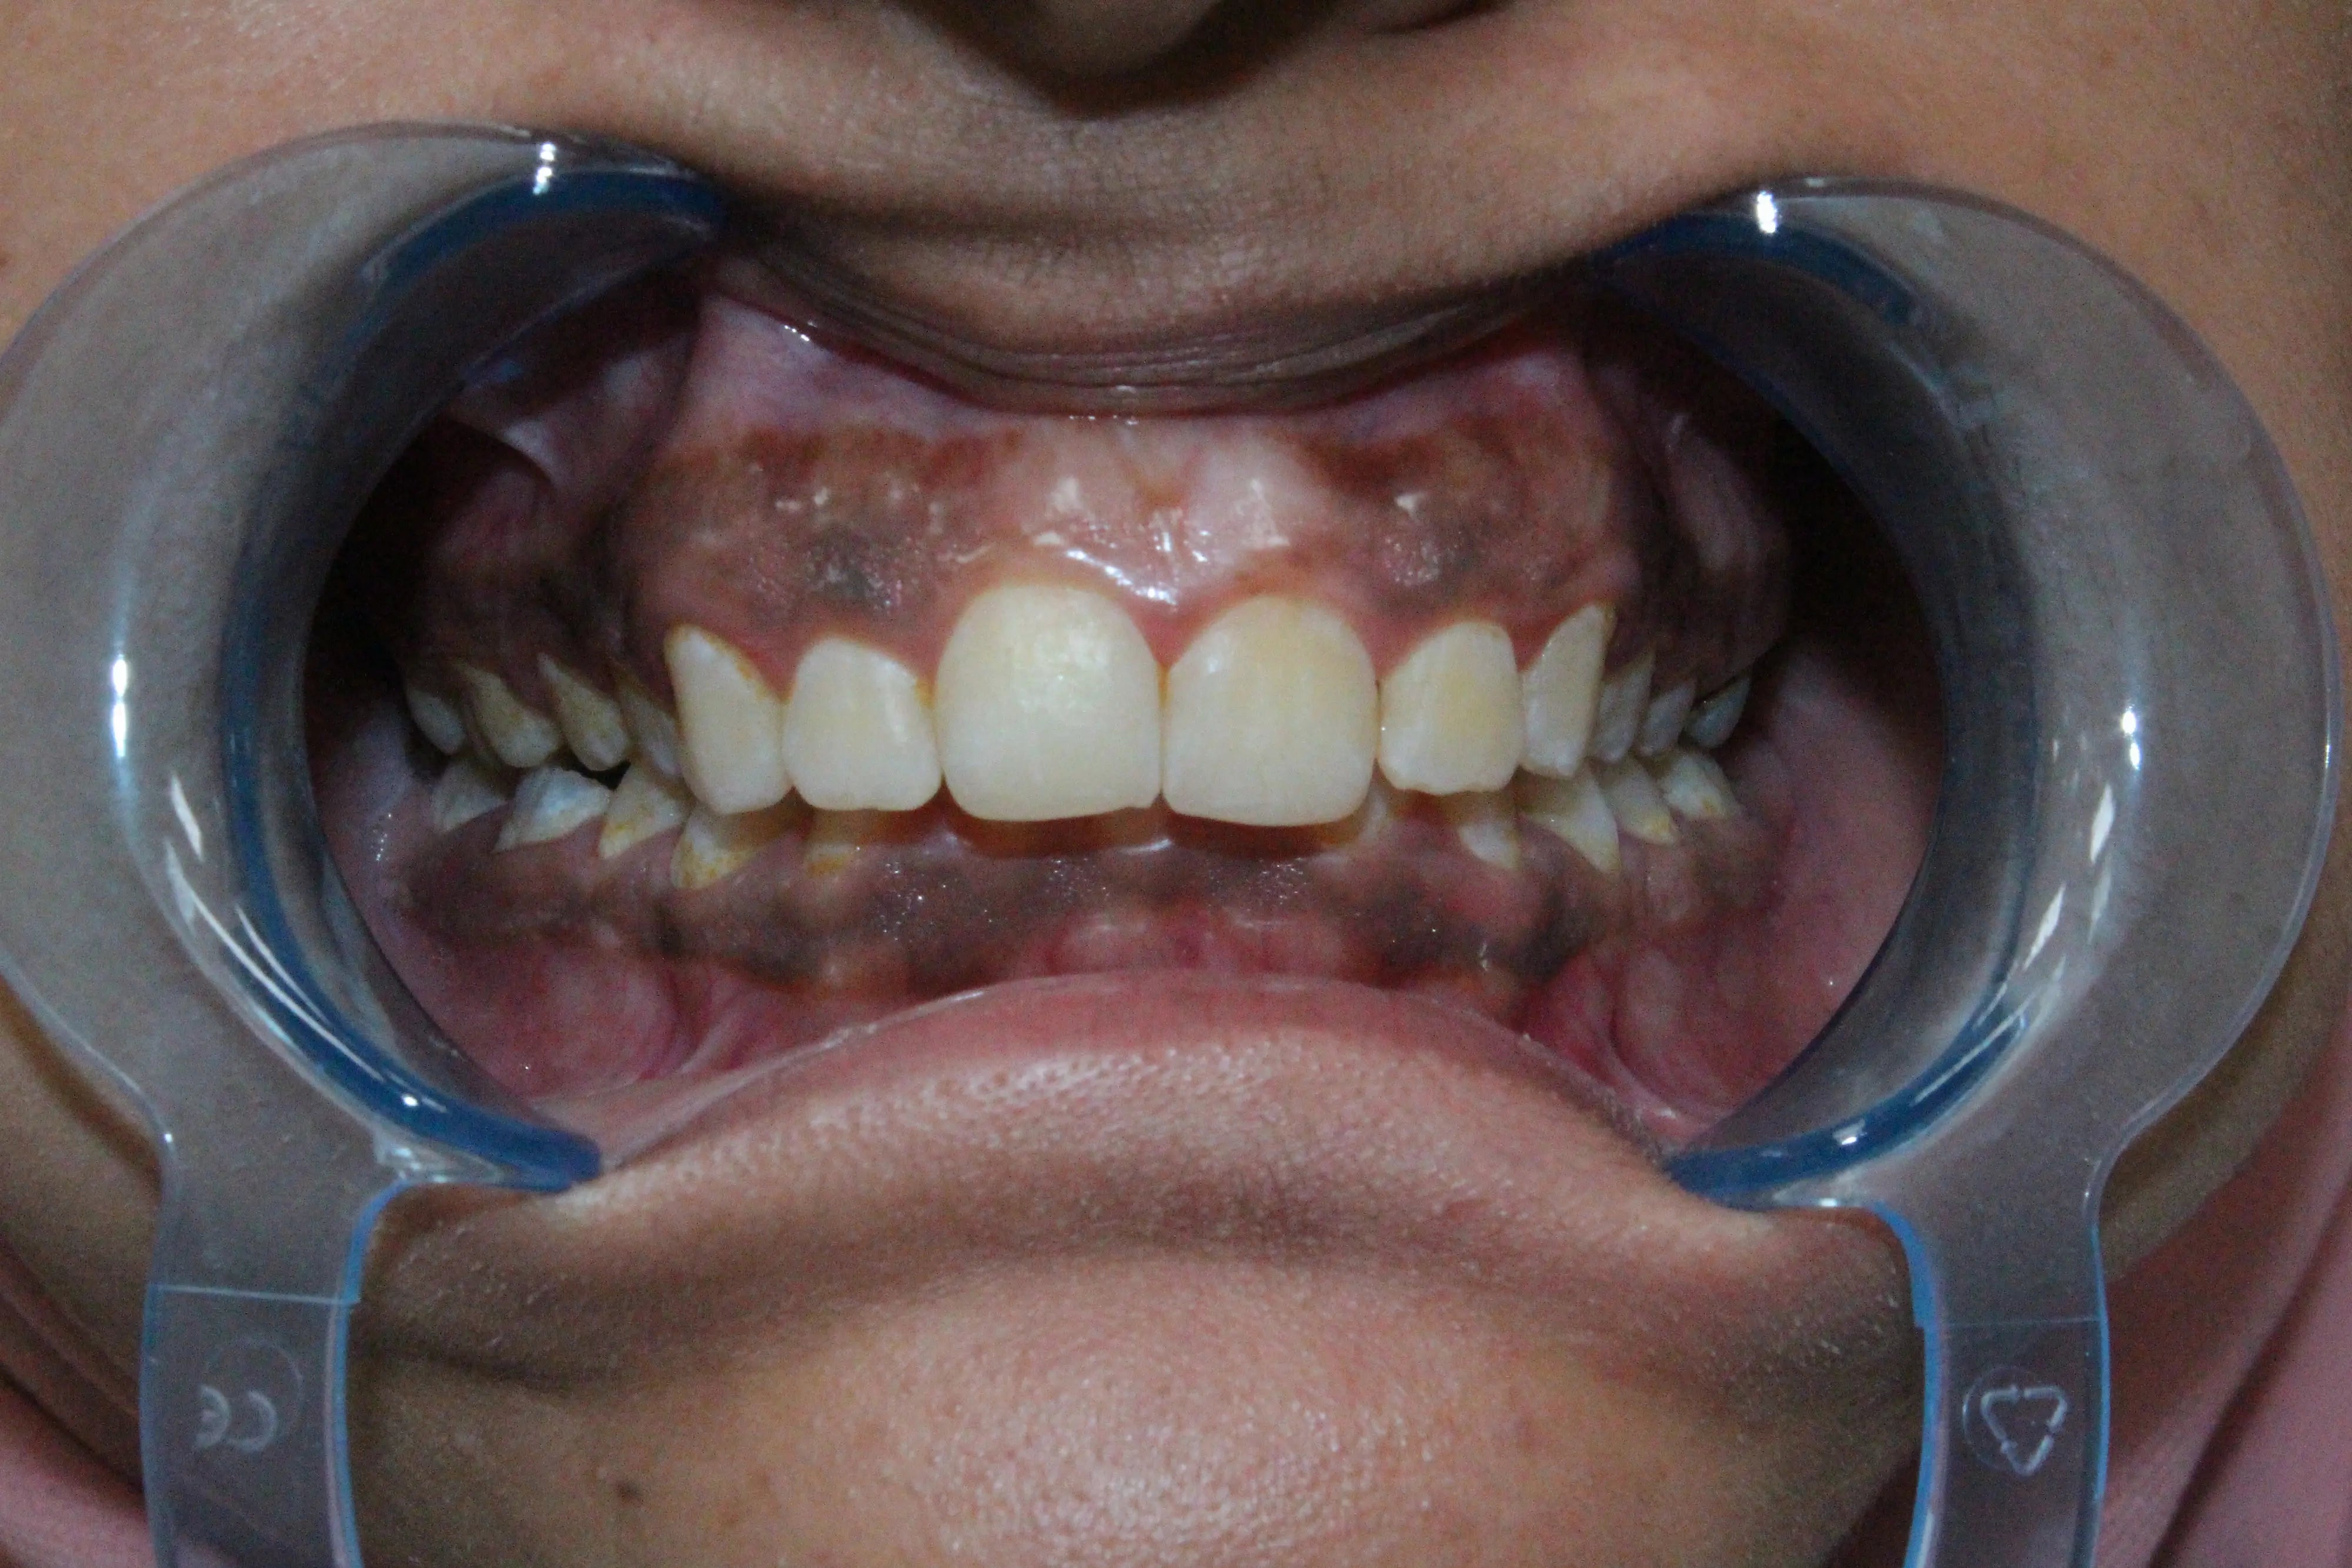

Let's start with the basics. Gum hyperpigmentation - also called gingival hyperpigmentation - is the medical term for darkening of the gum tissues. Think of it as the oral equivalent of having freckles or age spots on your skin.

This darkening typically occurs when there's an increased deposit of melanin (the same pigment that gives your skin and hair their color) in the gum tissue. Sometimes it's caused by changes in blood vessels, medications, or underlying medical conditions.

For many people, darker gums are simply part of their natural coloring. This is especially common among individuals with darker skin tones. According to research published in the Journal of Periodontology, melanin pigmentation in gingival tissue is a normal physiological variation and appears more frequently in certain ethnic populations.

Think of it this way: just as people have different skin tones, they also have varying levels of melanin in their gum tissue. There's nothing abnormal about this - it's simply genetic diversity at work.